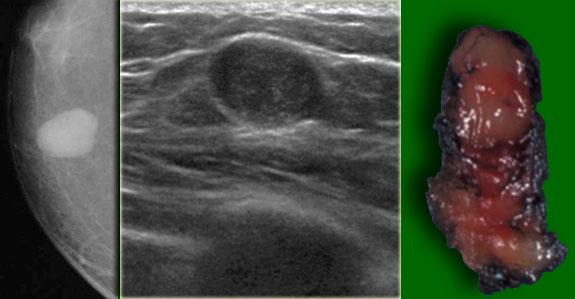

Bên trái là một tổn thương lớn, trông giống u xơ tuyến.

Tuy nhiên, chúng ta đã biết rằng nam giới không bị u xơ tuyến.

Kết quả giải phẫu bệnh là u cơ xơ bào và tổn thương được điều trị bằng phẫu thuật cắt bỏ tại chỗ.

Bên trái là một trường hợp u cơ xơ bào khác.

Tổn thương biểu hiện là một khối có múi, bờ rõ, không có vôi hóa.

Lưu ý rằng tổn thương nằm lệch tâm so với núm vú.

Khối có múi này mới cần được sinh thiết, không phải tổn thương vú to nam giới vùng sau núm vú.